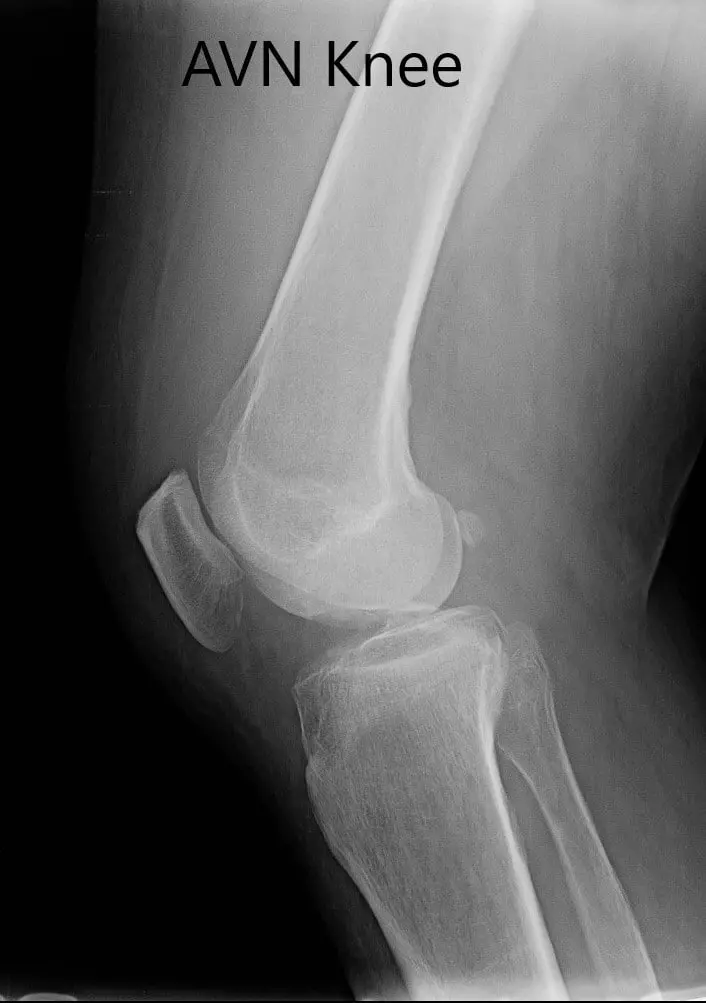

Preoperative X-ray of the right knee in anteroposterior and lateral views

Preoperative X-ray of the right knee in anteroposterior and lateral views - img 2

Preoperative X-ray of the right knee in anteroposterior and lateral views.